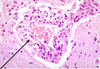

Neuronophagia

Neuronophagia “eating neurons”

- Phagocytosis of neurons by microglia/monocytes

- Hallmark in some viral infections